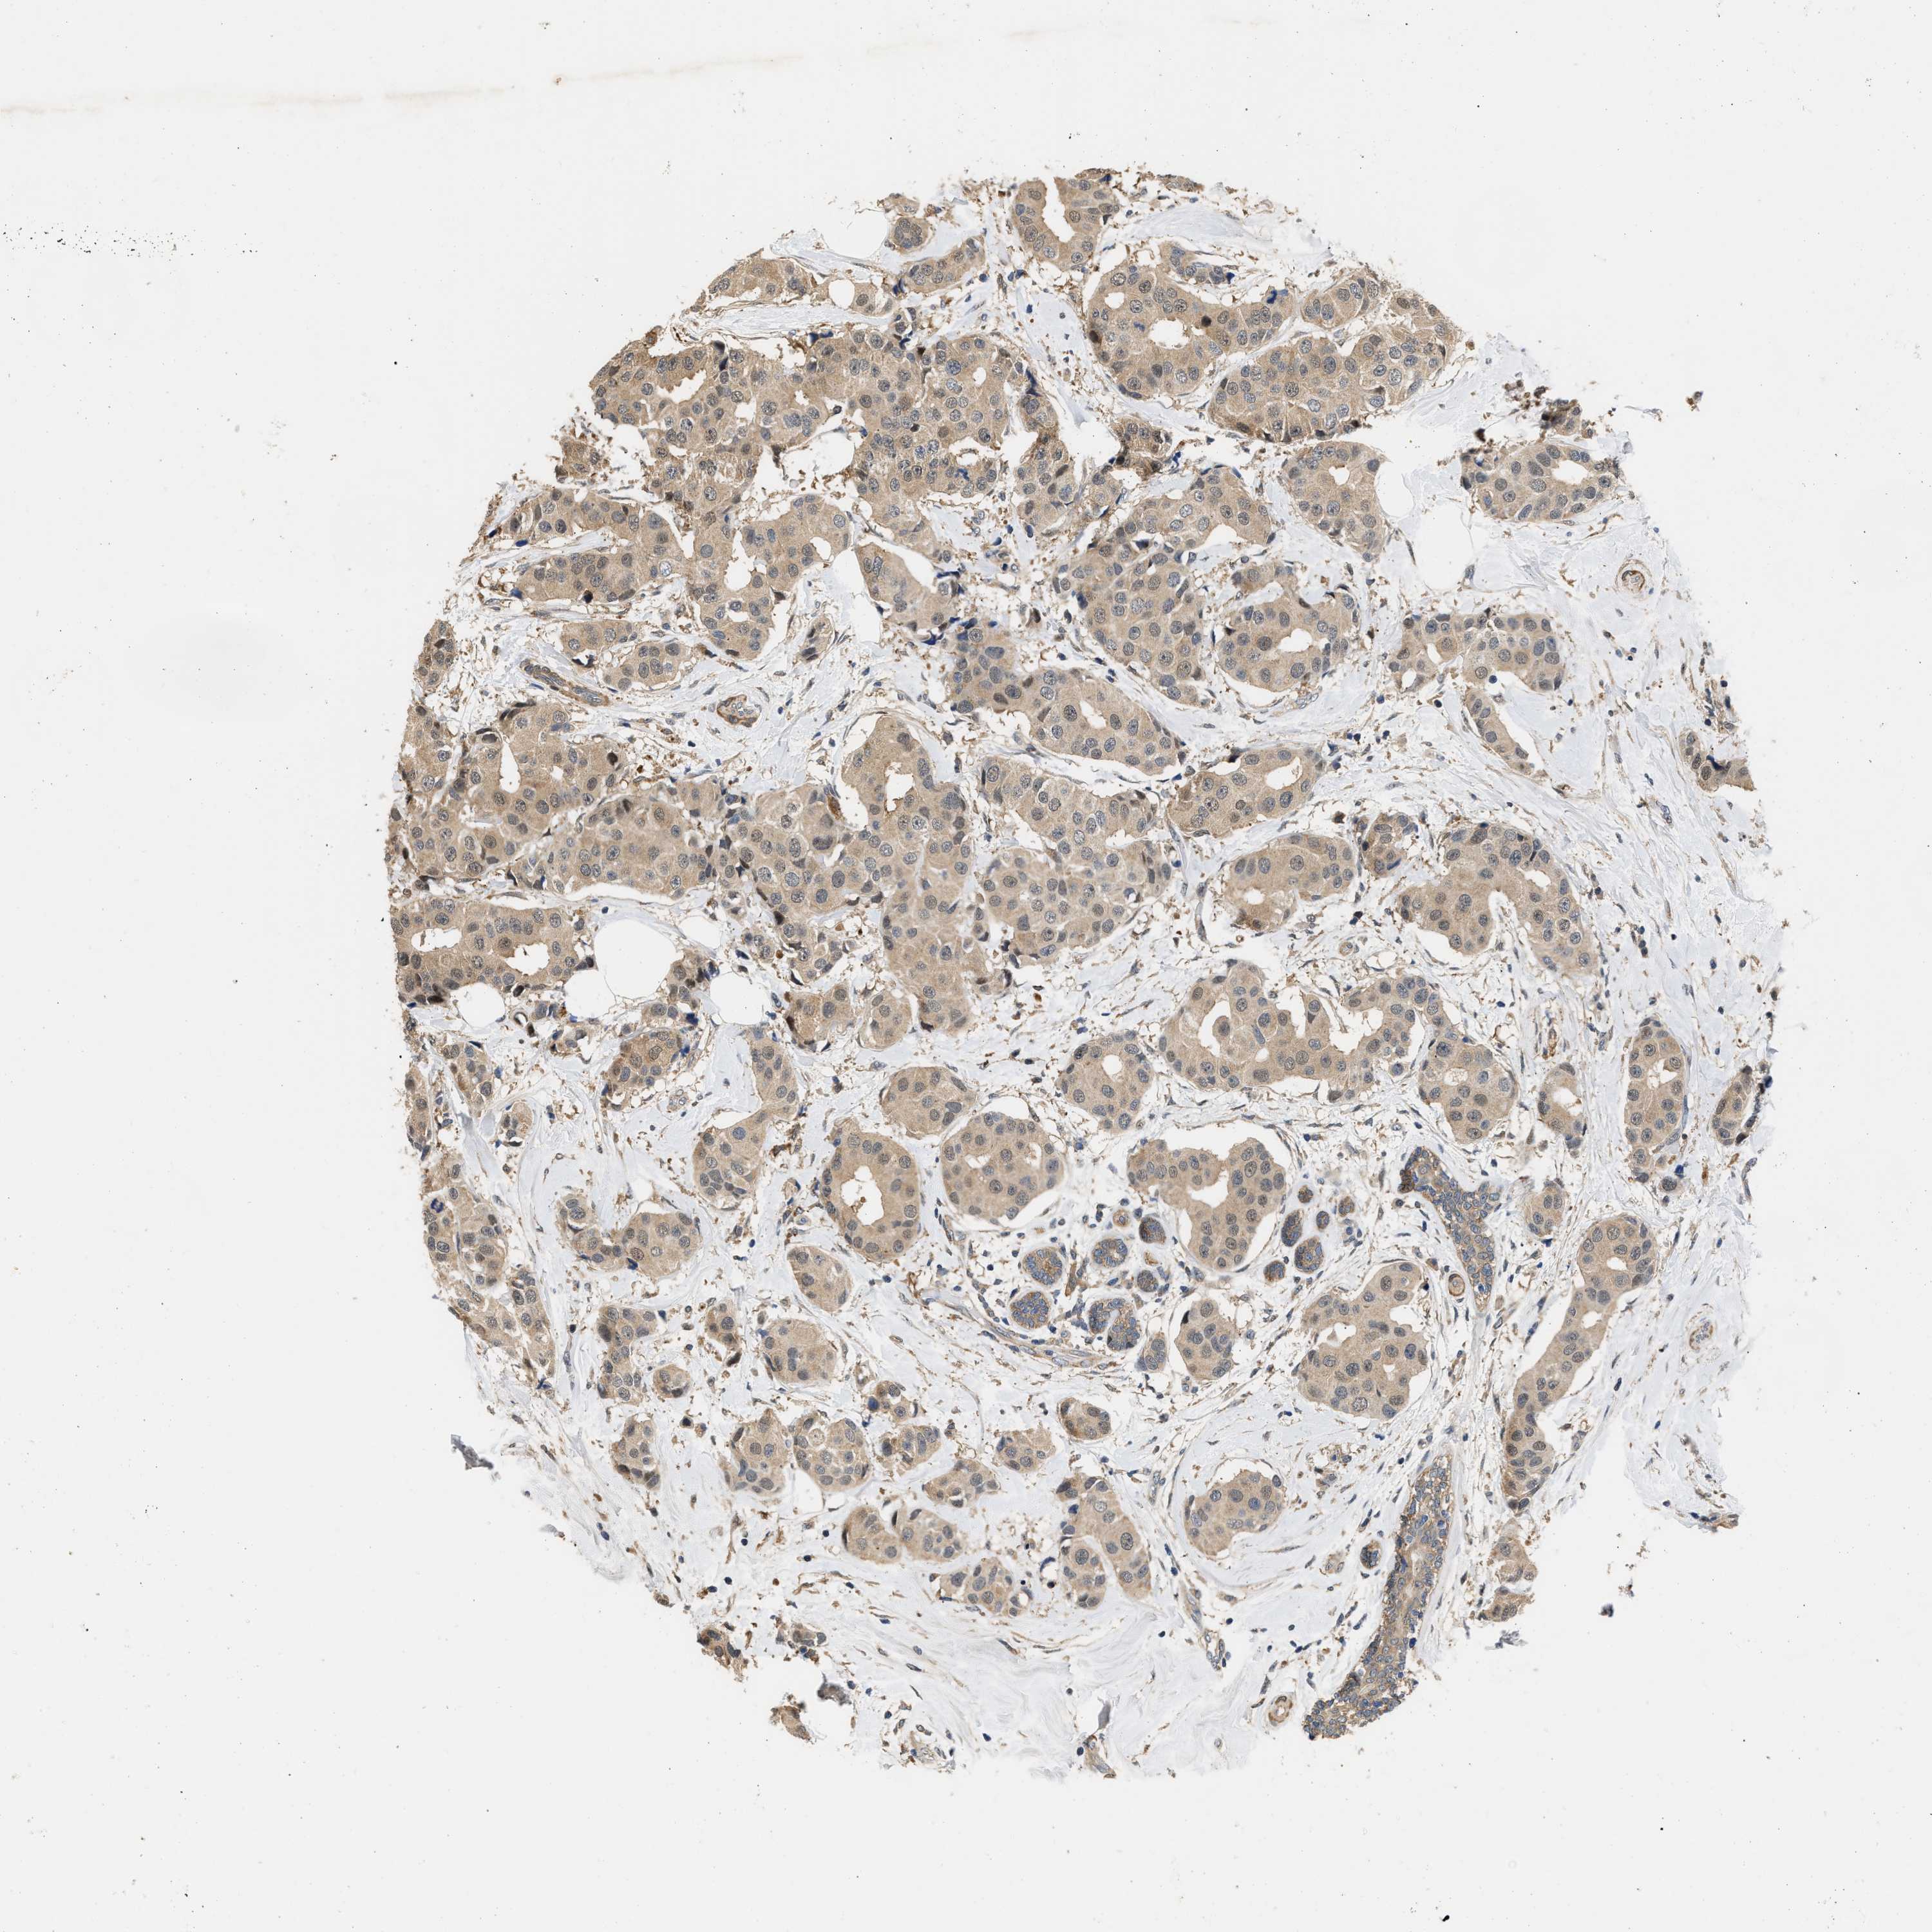

BRCA TCGA BRCA VALIDATION PROTEIN EXPRESSION